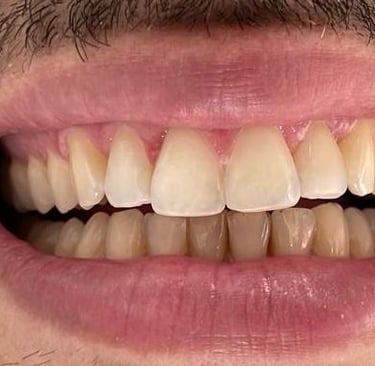

Coroas em Dissilicato de Lítio

Todos os caso a seguir estão associadas a clareamento dentário

Cirurgia de aumento de coroa clínica antes das coroas

Caso que demonstra a vantagem da integração de diversas áreas da odontologia, unindo cirurgia, periodontia, prótese e estética para alcançar resultados funcionais e harmônicos.

Antes

Depois